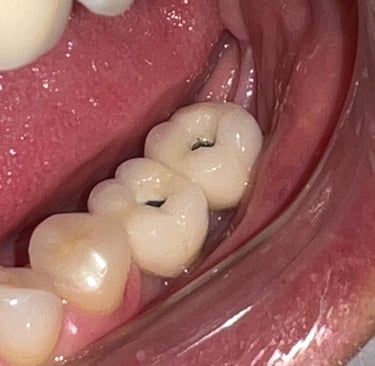

Aspecto clínico final - Imagens originais — nenhuma contém retoques